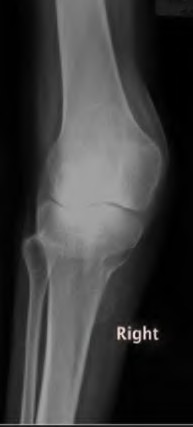

A 55-year-old male presents with isolated medial compartment osteoarthritis of the right knee. He is being evaluated for a medial unicompartmental knee arthroplasty (UKA). Which of the following physical examination or radiographic findings is an absolute contraindication to a medial UKA?

Which of the following is traditionally considered an absolute contraindication to a medial mobile-bearing unicompartmental knee arthroplasty (UKA)?